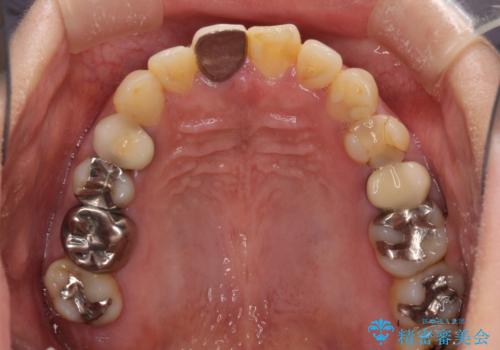

- 右下の欠損部の治療を希望して来院された患者様です。

部分矯正を行った後にインプラント埋入と手前の歯の根管治療を行い、その後補綴治療を行うこととしました。

治療途中より、上の歯や反対側の銀歯、上顎前歯の色合いや下顎前歯のデコボコが気になってきたため、全てを治療することとしました。